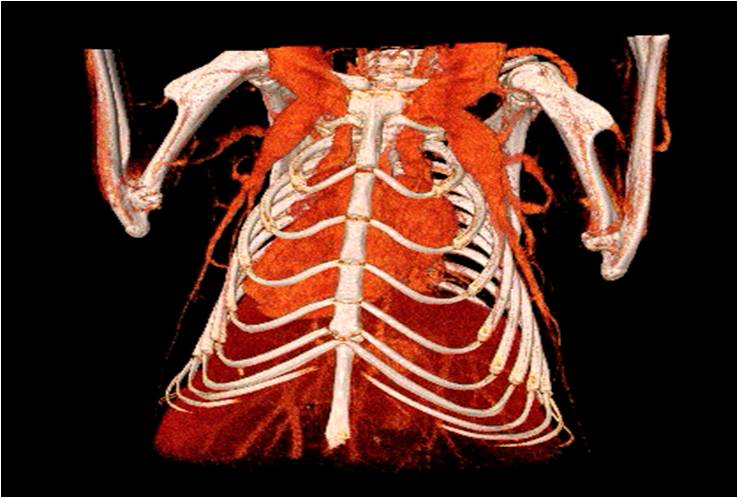

胸部和心血管的層析成像 胸部和心血管的3D圖像